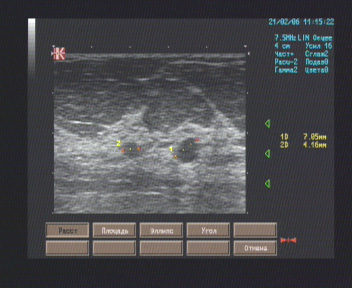

Эхографические признаки кист молочных желёз.

Молочные железы симметричные, больших размеров, кожные покровы не изменены, втяжение сосков не отмечается. Позадисосковая область визуализируется в косых проекциях, типичного строения. В наружном верхнем квадранте правой молочной железы, на 10 часах в 4-5 см. от соска лоцируется на глубина до 1,5 см. жидкостная гладкостенная полость диаметром 7 мм., не имеющая внутренних отражений. В верхнем внутреннем квадранте левой молочной железы, на 9 часах лоцируются две жидкостные полости диаметром 4 мм. и :,5 мм. с ровными чёткими контурами, не имеющие внутренних отражений. На остальном протяжении дифференциация тканей молочных желез хорошая, представлены преимущественно жировой тканью с прослойками фиброгландуллярной, диаметр млечных протоков 1 – 2,5 мм. Диффузных и очаговых патологических изменений не обнаруживается.

Лимфоузлы и лимфатические протоки в регионарных зонах лимфооттока не визуализируются.